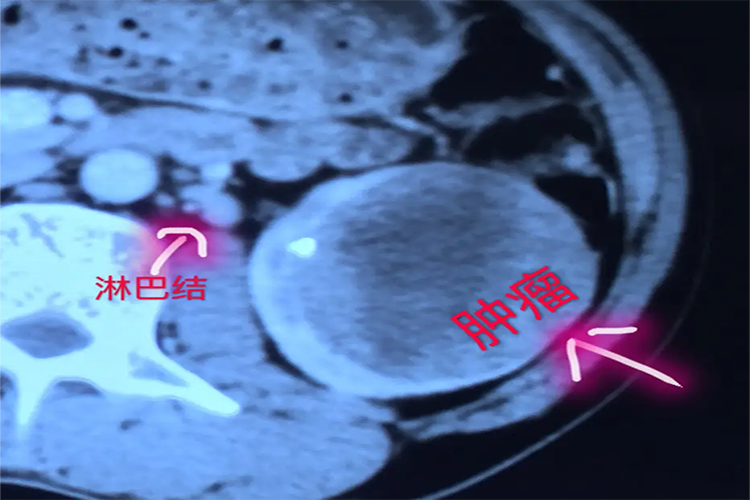

直接播散:肾细胞癌直接播散可以向外穿过肾脏被膜到肾周围组织或侵入肾静脉及下腔静脉。

淋巴转移:肾细胞癌约有15%-30%通过淋巴途径转移。左侧转移到肾蒂、主动脉前和左侧淋巴结;右侧累及肾门附近、下腔静脉前淋巴结、主动脉和下腔动脉间淋巴结,向上可转移到颈部引起颈淋巴结肿大等。